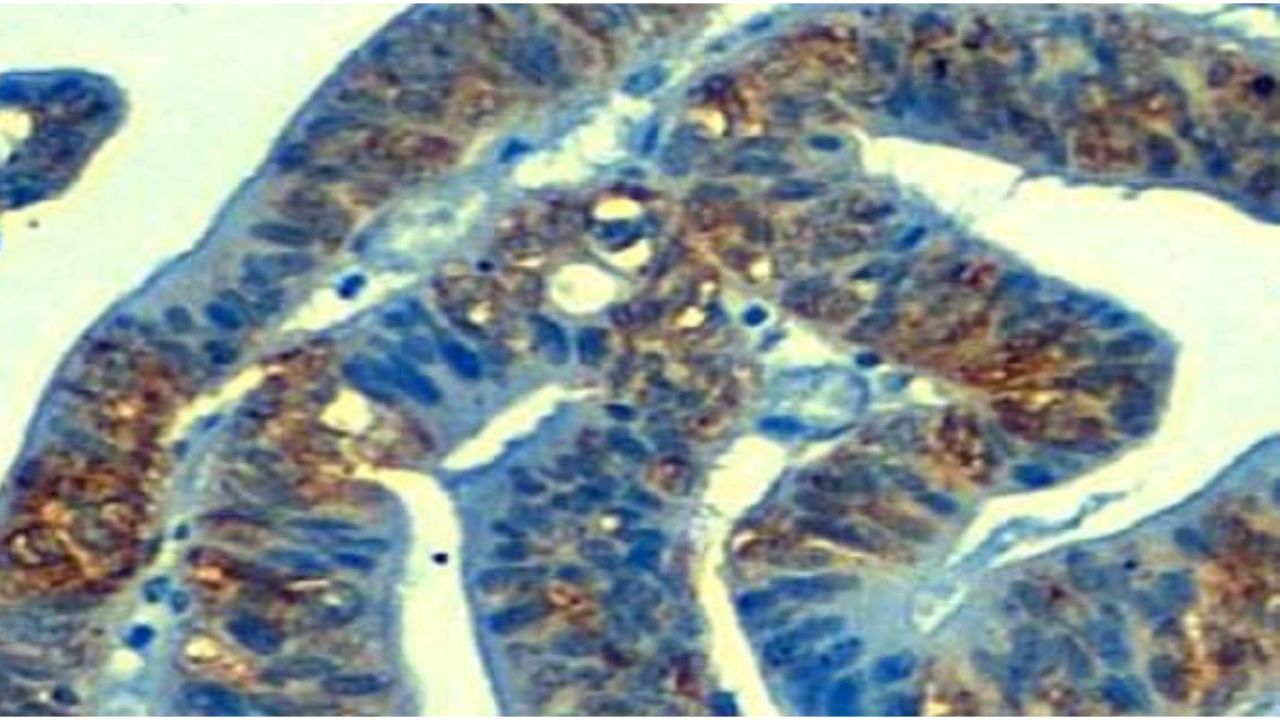

"Hemos encontrado que un 10% de tumores de colon y estómago presentan la pérdida de una molécula denominada TP53TG1, cuya función en células sanas es prevenir la activación de la proteína YBX1. Sin la vigilancia de TP53TG1 en estos tumores gastrointestinales, YBX1 se encarga de ir al núcleo de la célula y activar centenares de oncogenes que impedirán la muerte de las células malignas que inducen los fármacos antitumorales,” comenta Manel Esteller.

El espectro de resistencias inducidos por este mecanismo es extenso e incluye fármacos usados en el tratamiento común de este tipo de cánceres como el 5-fluorouracilo, el oxiplatino o el irinotecán, pero también medicamentos dirigidos a dianas moleculares recientes tales como los inhibidores de quinasas.